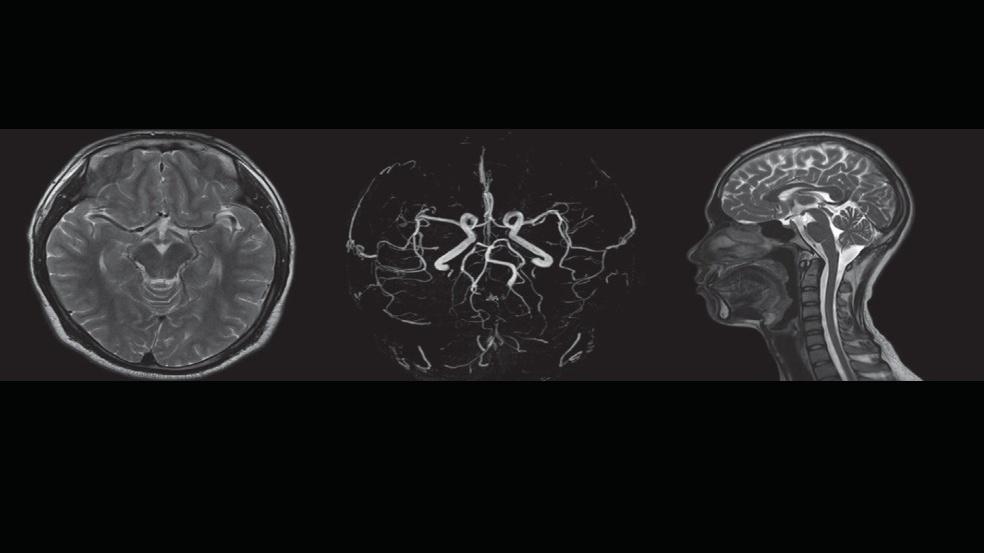

■자기공명영상(MRI)

인체를 구성하는 물질의 자기적 성질을 측정하여 컴퓨터를 통해 재구성하고, 영상화하는 진단 방법입니다.

강력한 경사자장 – Gemini Gradient : 200 mT/m의 강력한 경사자장과 보다 나은 촬영 기법을 통해 신속하고 정확한 진단이 가능한 프리미엄 3T MRI 입니다.

고화질 확산 강조 영상 획득 : 고화질 확산 강조 영상을 이용해 뇌 뿐만 아니라 복부, 척추, 관절 등에서도 확산영상을 얻어 전이성 악성 병변의 판별이 더욱 용이합니다.

수 많은 임상 영역에서 Thin slice 영상촬영 가능 : 머리, 다발성경화증, 경추, 요통, 골반 및 복부질환 등 복잡한 임상 영역에서 Thin slice 영상촬영이 가능하여 선명한 화상 이미지를 얻어 정확한 진단이 가능합니다.